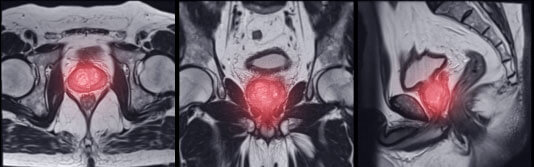

Vejiga Próstata

La prostatitis puede ser bacteriana o no bacteriana. En el primer caso, la enfermedad está causada por agentes patógenos (estafilococos, estreptococos), y en el segundo, por congestión pélvica.

La bebida Rico Boost es igualmente eficaz para diferentes formas y grados de prostatitis. Su fórmula es antibacteriana y antiinflamatoria. Actúa por igual contra los agentes causantes y los síntomas de la enfermedad.

Como resultado, la próstata se normaliza, así como la vida sexual del paciente.